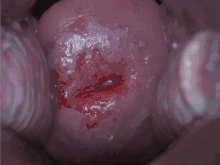

Confirmation of the diagnosis of cervical cancer or precancer requires a biopsy of the cervix. This is often done through colposcopy, a magnified visual inspection of the cervix aided by using a dilute acetic acid (e.g. vinegar) solution to highlight abnormal cells on the surface of the cervix,[5] with visual contrast provided by staining the normal tissues a mahogany brown with Lugol's iodine.[61] Medical devices used for biopsy of the cervix include punch forceps. Colposcopic impression, the estimate of disease severity based on the visual inspection, forms part of the diagnosis. Further diagnostic and treatment procedures are loop electrical excision procedure and cervical conization, in which the inner lining of the cervix is removed to be examined pathologically. These are carried out if the biopsy confirms severe cervical intraepithelial neoplasia.[62][63]

The location of cervical cancer can be described in terms of quadrants, or corresponding to a clock face when the subject is in supine position.